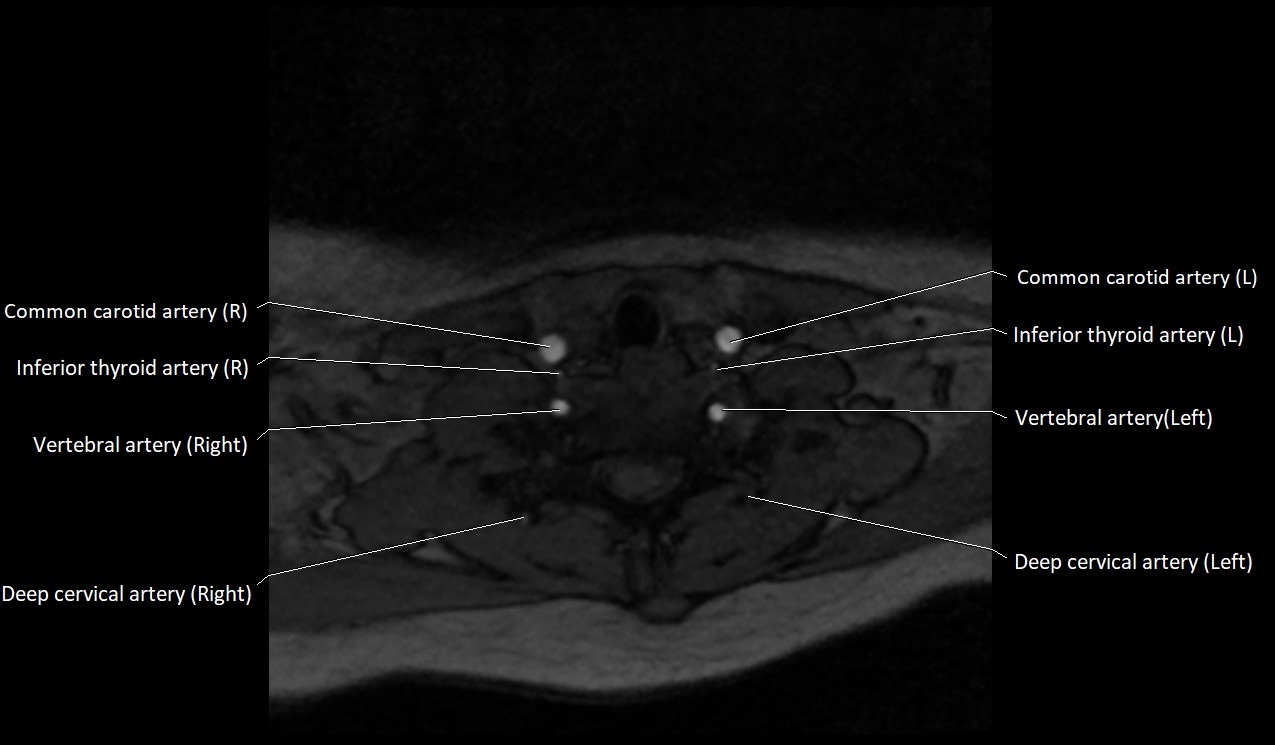

MRI images

image